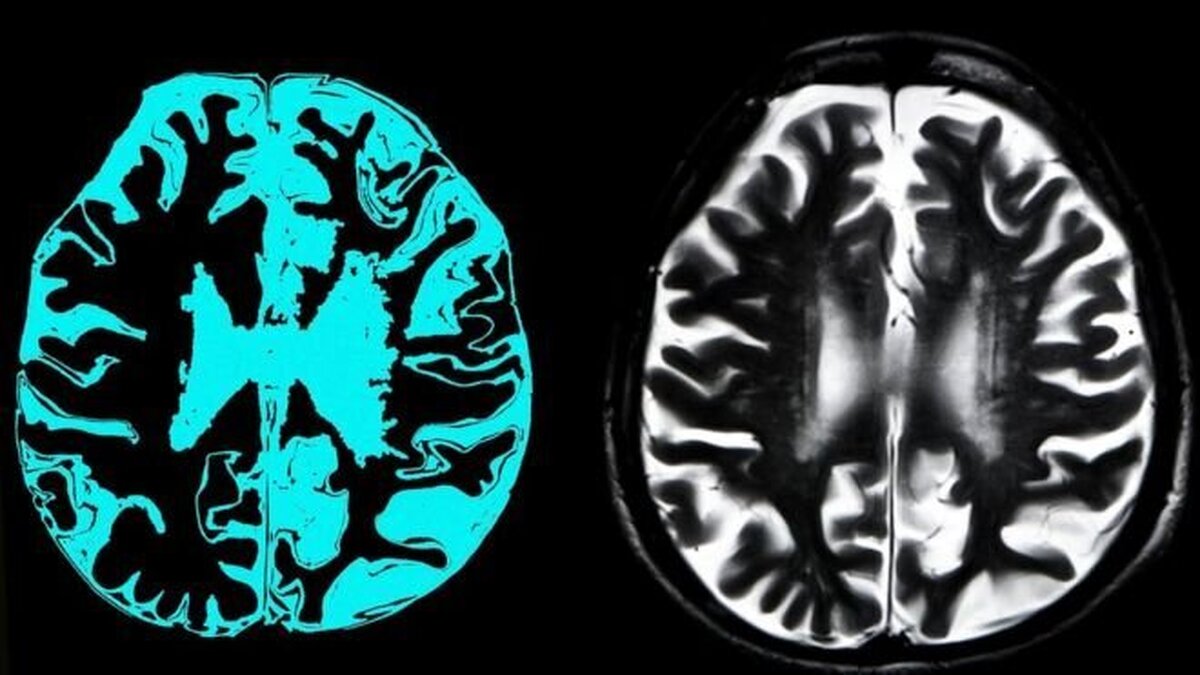

به گزارش فرارو به نقل از بلومبرگ، سه دهه از زمانی که دانشمندان فرض کردند آلزایمر ناشی از تجمع پروتئین بتا آمیلوئید در مغز است میگذرد. ماه گذشته داروسازان به موفقیت بزرگی دست یافتند. شرکت داروسازی ژاپنی "ایزای" همراه با شریک خود شرکت داروسازی امریکایی "بایوژن" (Biogen Inc) نتایج یک آزمایش در مقیاس بزرگ را منتشر کردند که نشان میداد آن دو شرکت توانستهاند پیشرفت بیماری آلزایمر را کاهش دهند.

اگر بیمارانی که در وضعیت وخیم هستند نتوانند داروی جدید را بخرند ما به خاطر آن مورد انتقاد قرار خواهیم گرفت. داروهای ابتکاری تنها در صورتی مهم هستند که بیماران بتوانند آن را مصرف کنند. زمانی نوبت به قیمت گذاری میرسد مهم است که مقرون به صرفه بودن قیمت دارو در هر کشور را در نظر بگیرید. نکته دیگر آن است که بیماران برای استفاده از لکانمب باید رسوبات پلاک آمیلوئیدی در مغز داشته باشند. چنین تاییدی با تصویربرداری PET (توموگرافی انتشار پوزیترون) یا تجزیه و تحلیل مایع مغزی نخاعی انجام میشود. بیومارکرها (نشانگرهای زیستی) خون در دسترس هستند، اما به طور گستردهای برای جایگزینی به جای تصویربرداری PET یا تجزیه و تحلیل مایع مغزی نخاعی CSF)) پذیرفته نشدهاند. در مورد پوشش بیمهای باید چنین روشهای تشخیصیای نیز مورد بحث و بررسی قرار گیرند.